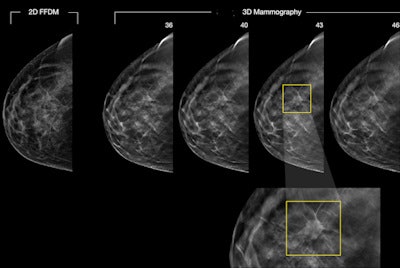

Many studies at ECR 2015 focused on synthesized mammography, or constructing 2D mammograms from DBT datasets using image-processing software. Several researchers have begun advocating the use of synthesized 2D images plus DBT, stating that they work as well as conventional 2D mammography plus DBT. Researchers have also continued to compare DBT with mammography in detecting calcifications and study the technology's impact on recall rates, masses, and more.

One thing's clear: Evidence continues to mount that DBT trumps mammography in many regards.